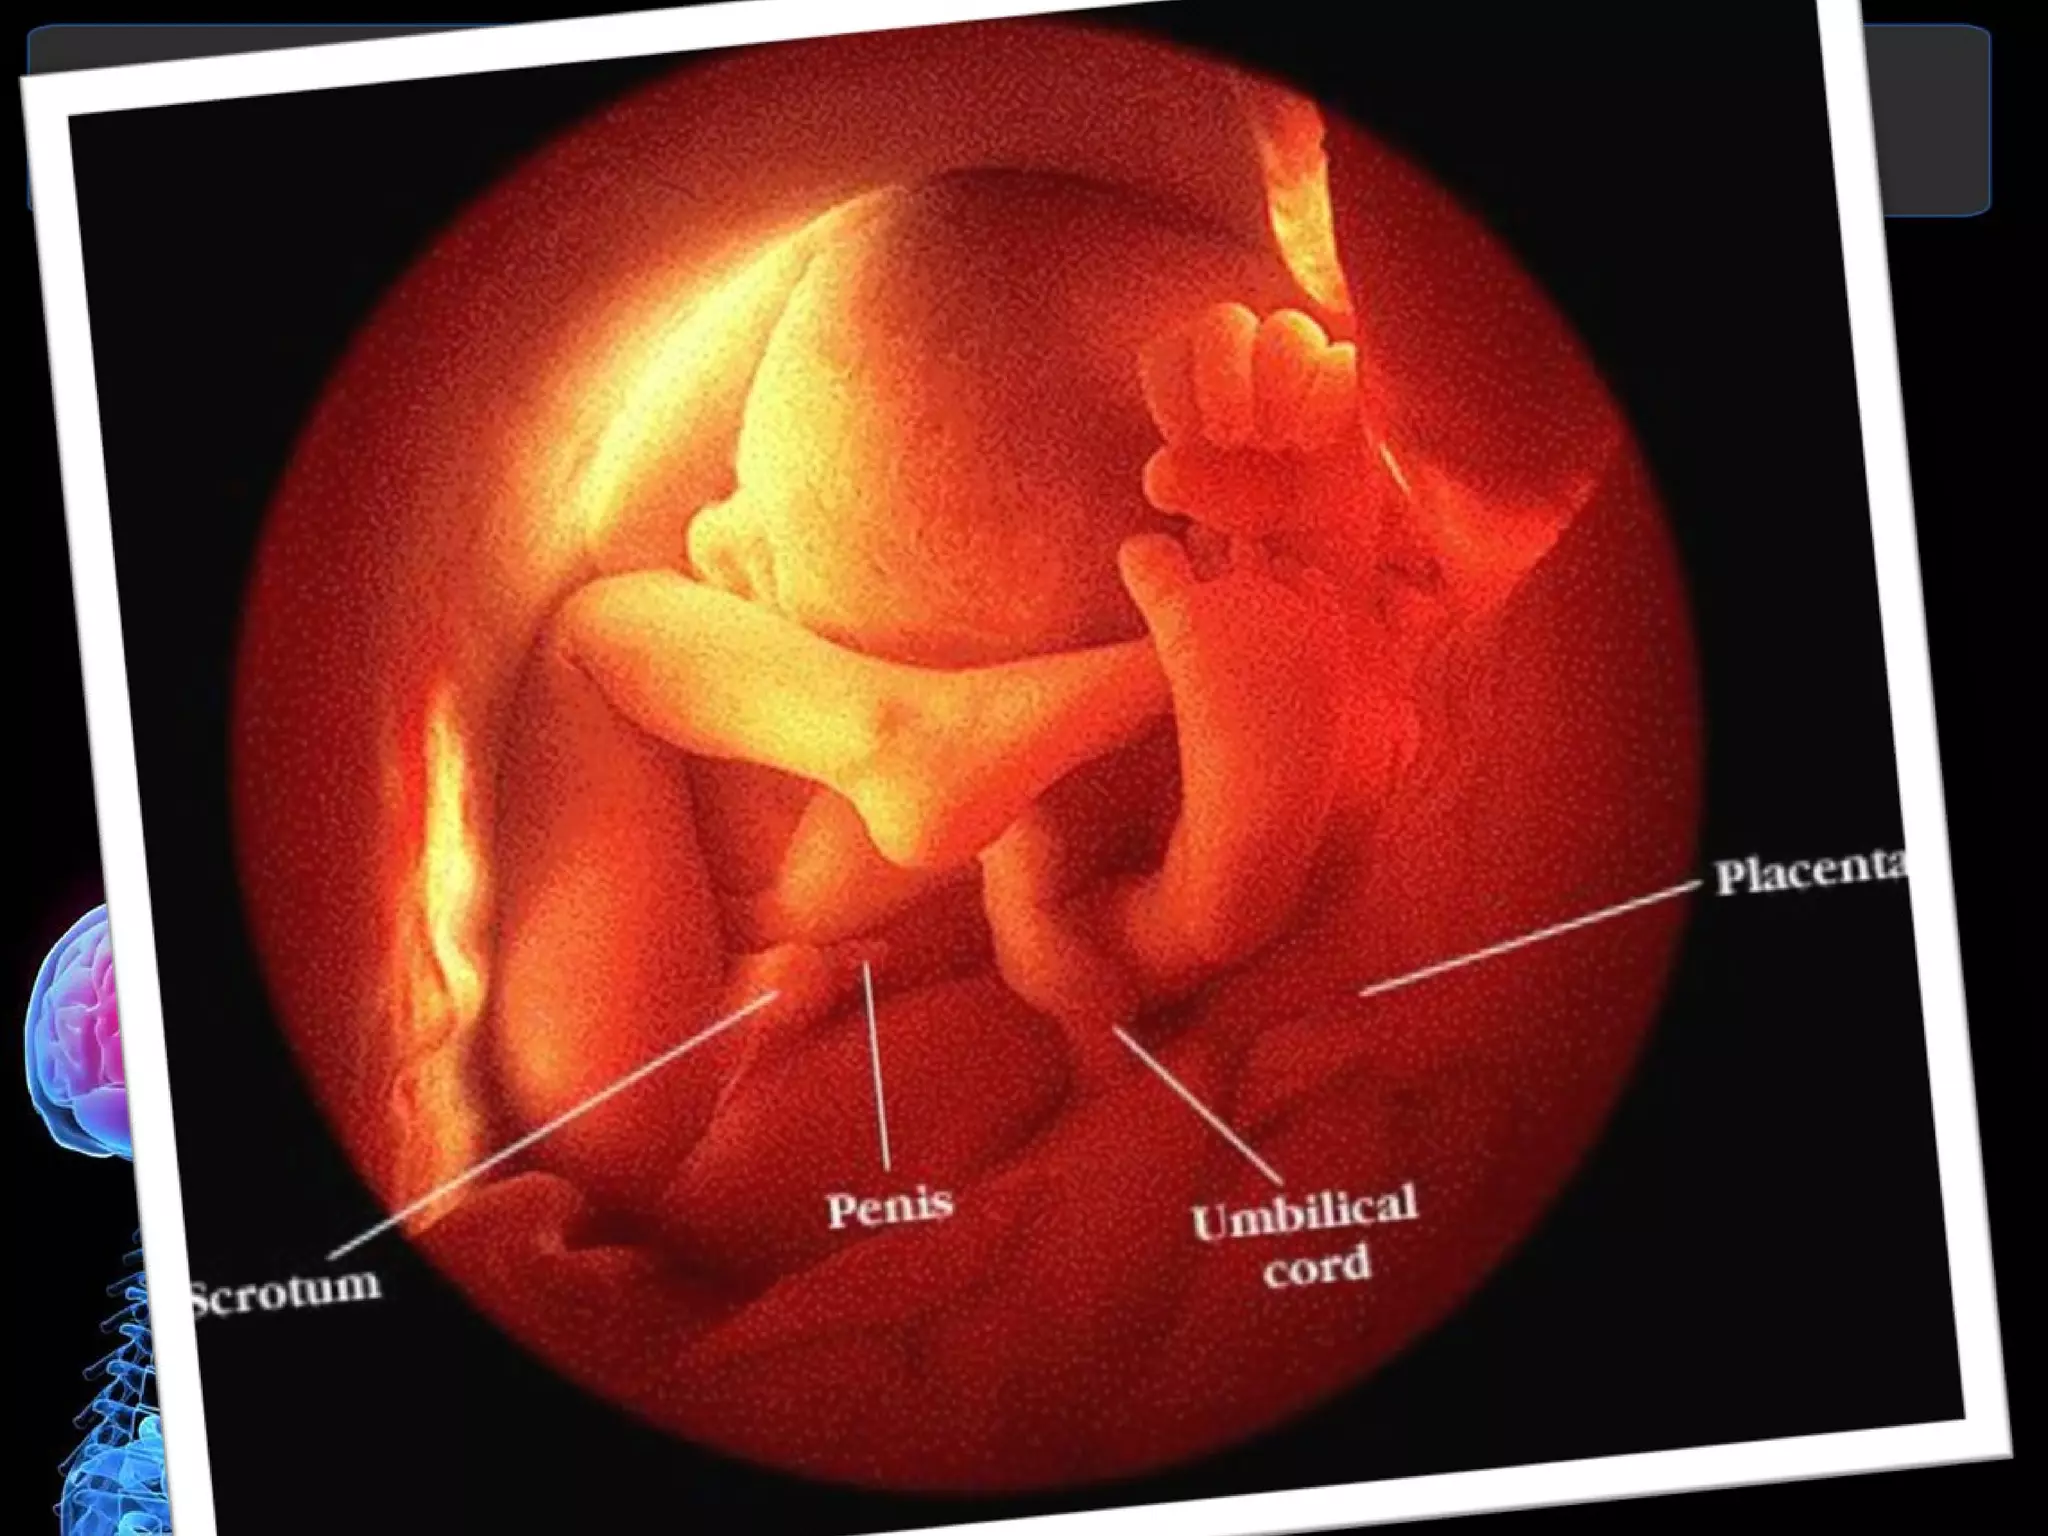

Month 2  First Trimester At the end of 8 weeks:   Baby is 1-1/8 inches long  Heart is functioning  Eyes, nose, lips, tongue, ears and teeth are forming  Penis begins to appear in boys  Baby is moving, although the mother can not yet feel movement

Month 4  Second Trimester At the end of 4 months:   Baby is 6 1/2 to 7 inches long  Weight is about 6 to 7 ounces  Baby is developing reflexes, such as sucking and swallowing and may begin sucking his/her thumb  Tooth buds are developing  Sweat glands are forming on palms and soles  Fingers and toes are well defined  Sex is identifiable  Skin is bright pink, transparent and covered with soft, downy hair  Although recognizably human in appearance, the baby would not be able to survive outside the mother's body

12 Weeks The fetus measures about two and a half inches and starts to make its own movements. You may start to feel the top of your uterus above the pelvic bone. Your doctor may hear the baby's heartbeat with special instruments. The sex organs of the baby should start to become clear.

16 Weeks The fetus now measures about 4.3 to 4.6 inches and weighs about 2.8 ounces. The top of your uterus should be felt about three inches below your belly button. The baby's eyes can blink and the heart and blood vessels are fully formed. The baby's fingers and toes should have fingerprints.